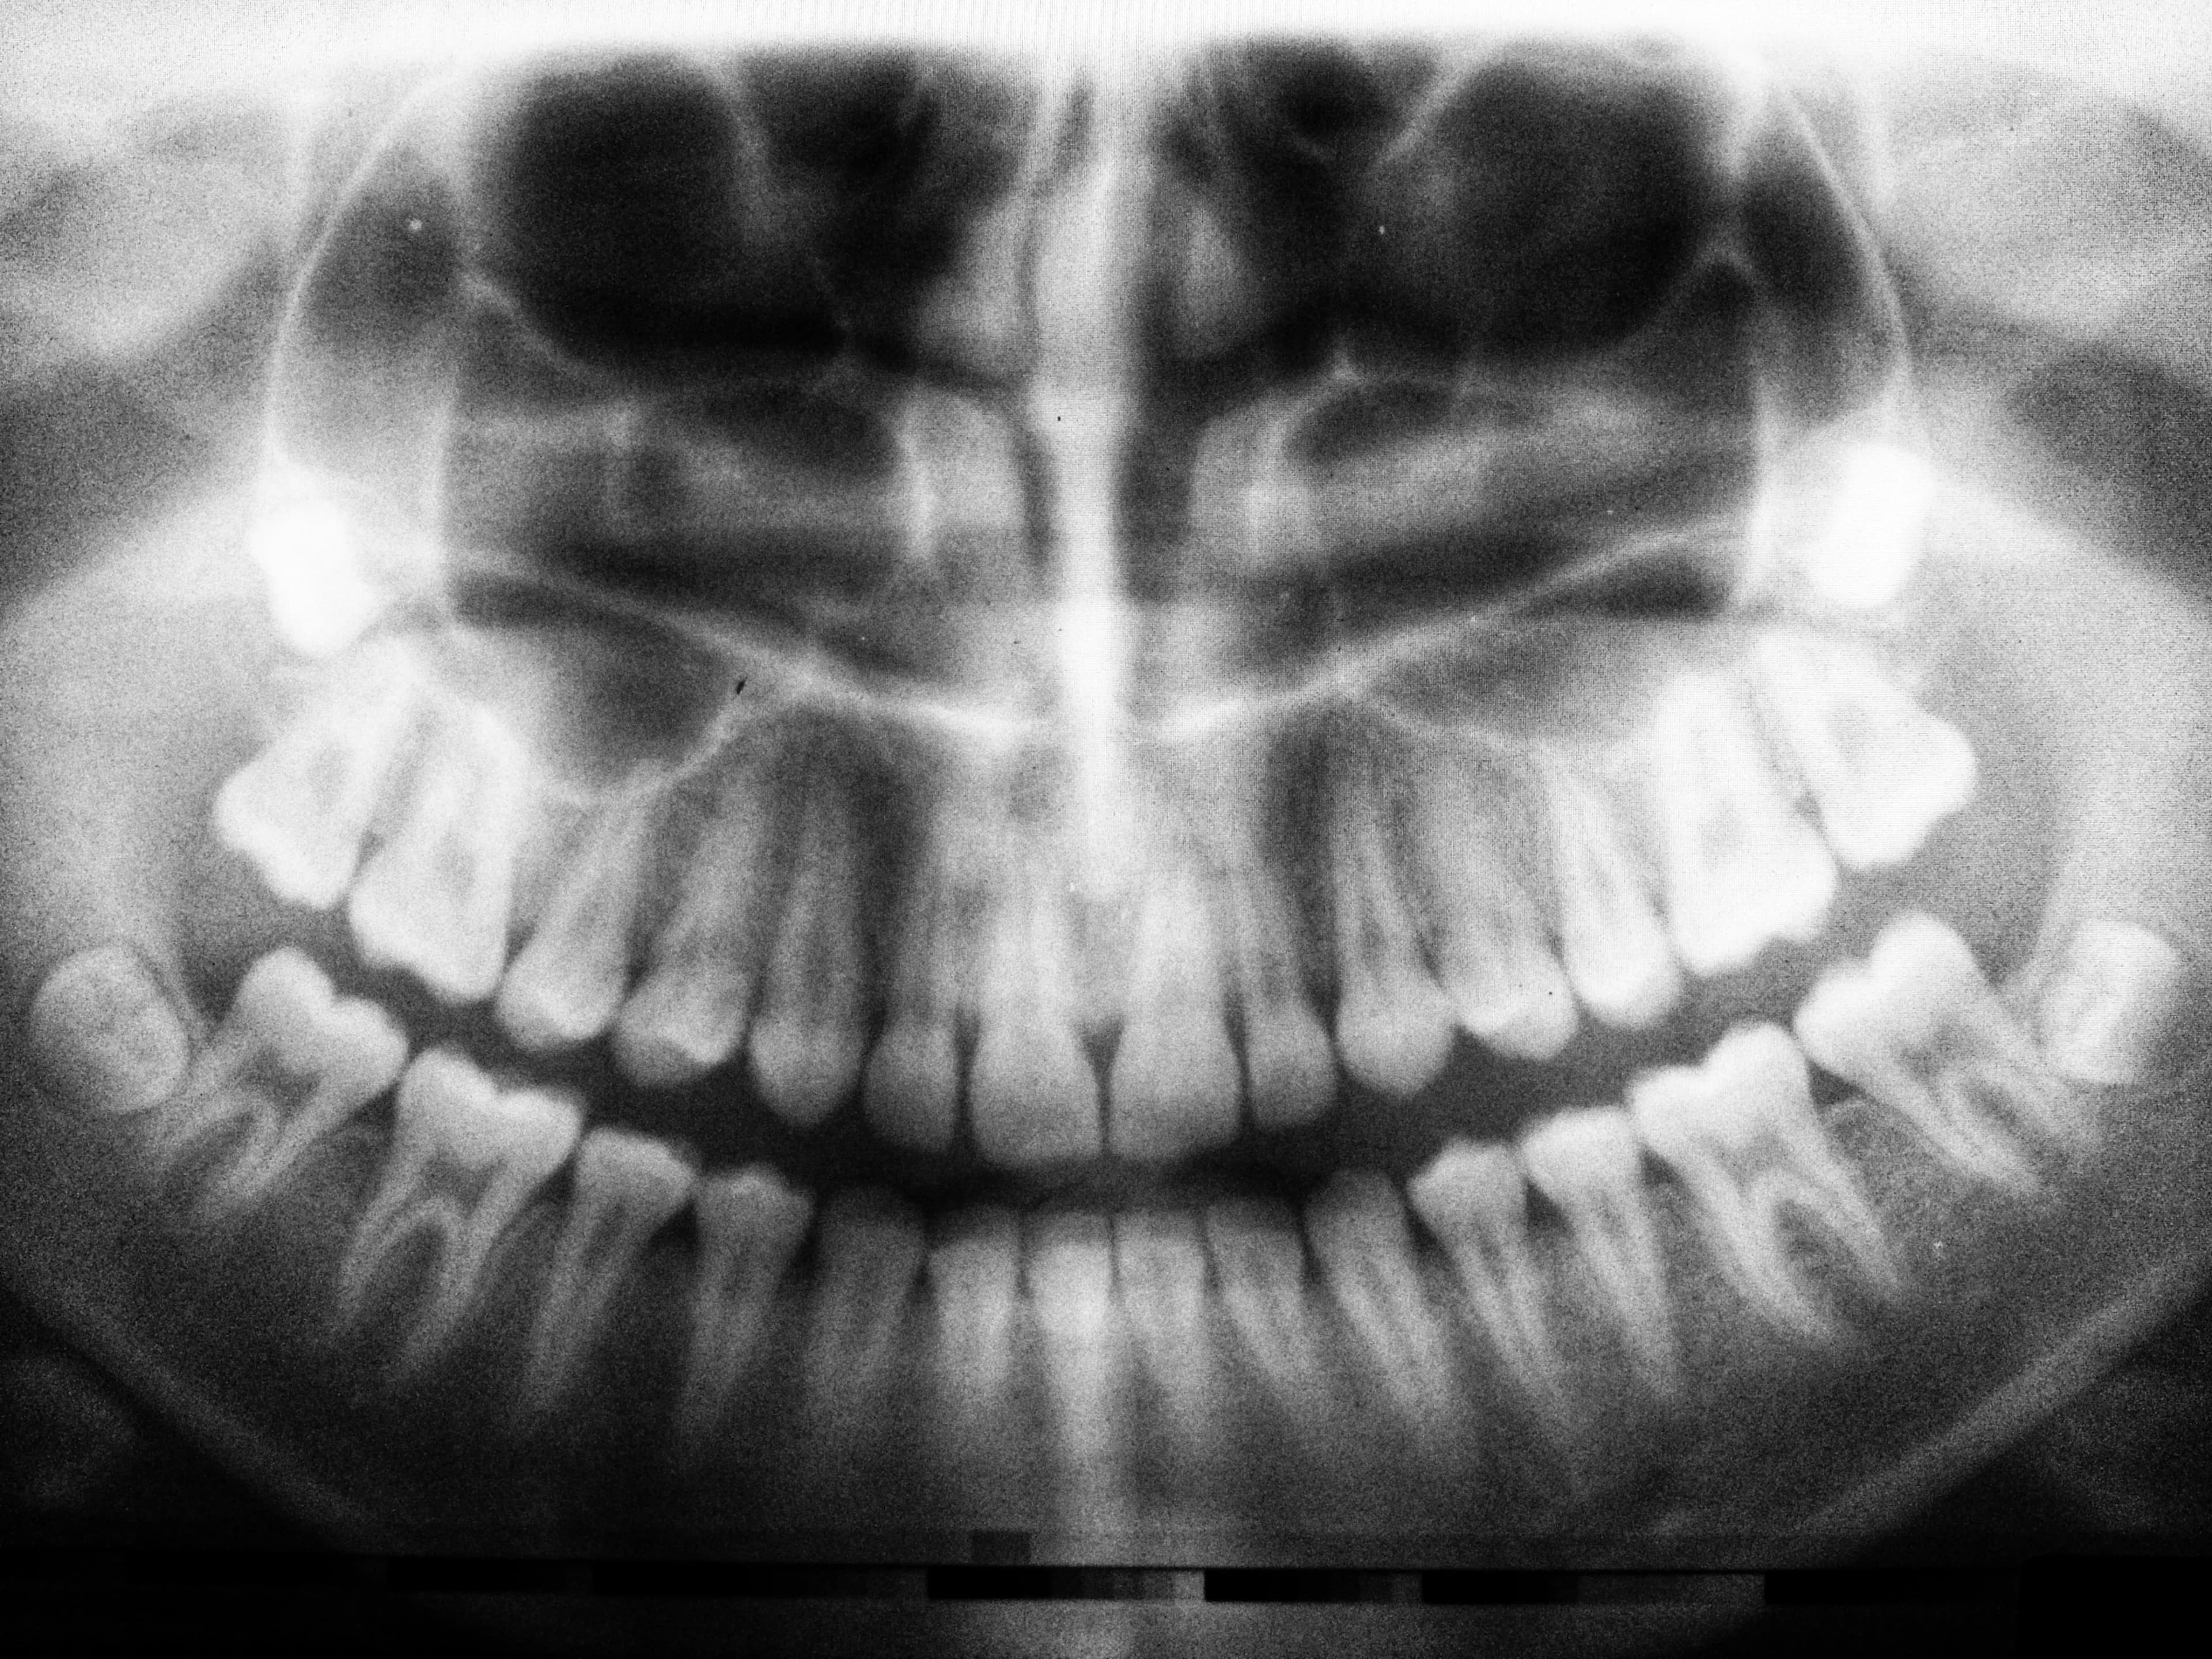

The oral and maxillofacial surgeon plays an essential role in treating oral pathologies, which can include a wide range of conditions affecting the tissues and structures of the mouth, jaw, and face. These pathologies can range from benign tumours to aggressive tumours and even malignant tumours. Early detection and management of certain conditions can have a significant impact on recovery and long-term prognosis. It may happen during a consultation with your dentist or family doctor that they notice an abnormality and are concerned about its nature. They will then send a consultation request for one of the surgeons on our team to examine you. After a thorough evaluation of the different structures of the face, oral cavity, jaws, and neck, and in some cases, taking x-rays, a biopsy may be necessary. A biopsy involves taking a tissue sample that is submitted for microscopic analysis by a pathologist. This can then help establish a treatment plan ranging from simple regular follow-ups to surgical treatment.